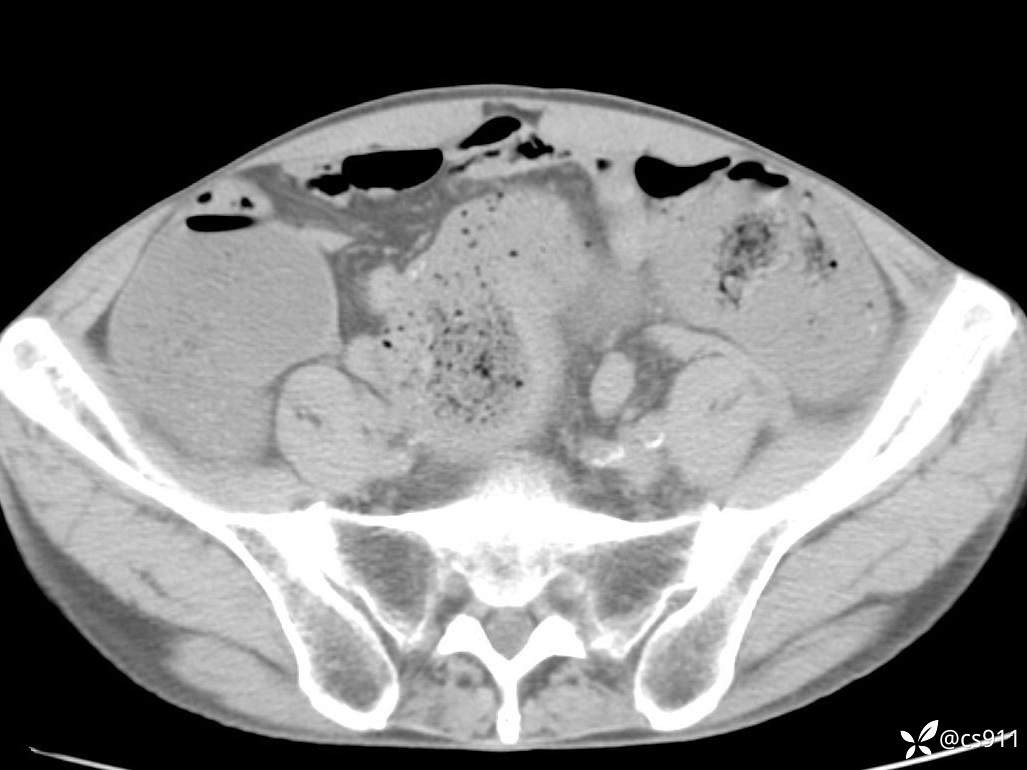

急腹症之急诊CT,原因?答案公布

男,77岁,腹痛、腹胀伴恶心呕吐1天。呕吐胃内容物,非喷射性呕吐,有咖啡色样胃内容物,诉有胃穿孔病史。查体:全腹平,下腹部压痛,全腹无反跳痛,叩诊呈浊音,移动性浊音阴性,肠鸣音减弱,1-2次/分。肛检:直肠未扪及明显肿物,可触及大量粪块。

T 36.6℃ P 80次/分 R 26次/分 BP 100/60mmHg

白细胞(WBC) H 14.55 10e9/L 4-10

中性粒细胞百分率(NEUT%) H 85.7 % 40-75

血淀粉酶(AMY) HH 1859 U/L 35-135

癌胚抗原(CEA) H 27.44 ng/ml 0-5

呕吐物 潜血试验 * 阳性 阴性

患者轮椅入室检查神志清楚, 能配合摆位和呼吸